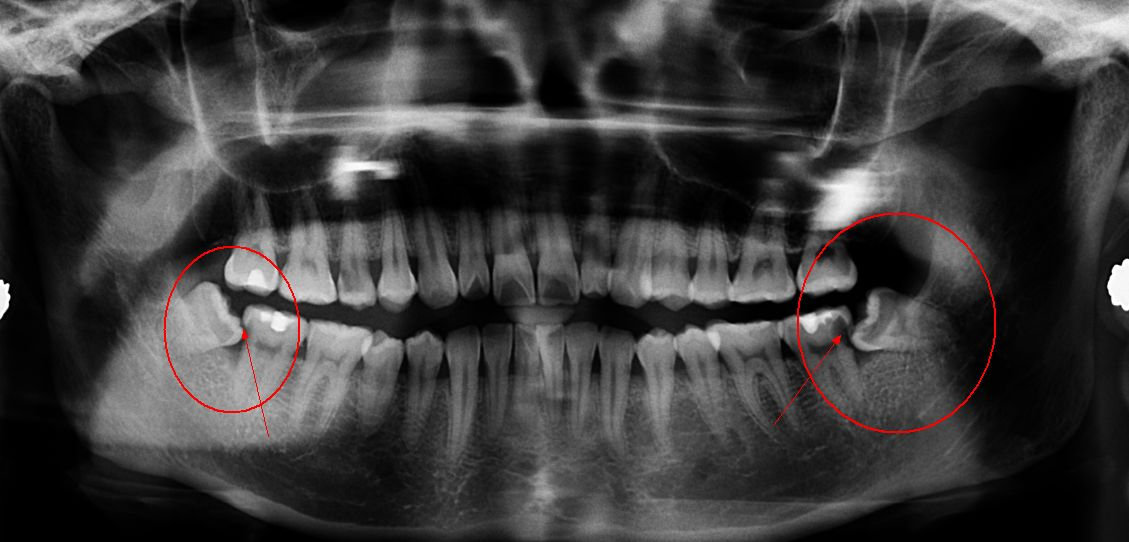

我们的口腔也在改变。它们变得越来越小,越来越接近子弹形状。但是牙齿变化并没有跟上,这就是为什么现在有人需要正畸和拔除智齿的原因。而出生时没有智齿或者智齿长出较晚的人也越来越多。在没有刀具和烹饪手段的时期,智齿的作用相当重要,当时人类可能会因为咀嚼坚硬的食物而失去臼齿,需要用智齿替代其功能。如今,35%的人没有智齿,而相关基因尚不清楚,因此我们还不太确定发生这种情况的原因。

智齿影像 图源:知乎专栏